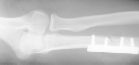

volar surface of the proximal forearm had two small puncture wounds . Radiographs

revealed a comminuted fracture of the proximal one-third of the ulna with

over-riding of the fragments. The radial head was dislocated anteriorly

.

The patient was taken to the

operating room where the wounds were extended with an incision and irrigated

with approximately six liters of fluid .After irrigation and debridement,

open reduction and fixation of the ulna with a four -hole plate was performed.

The radial head was reduced closed